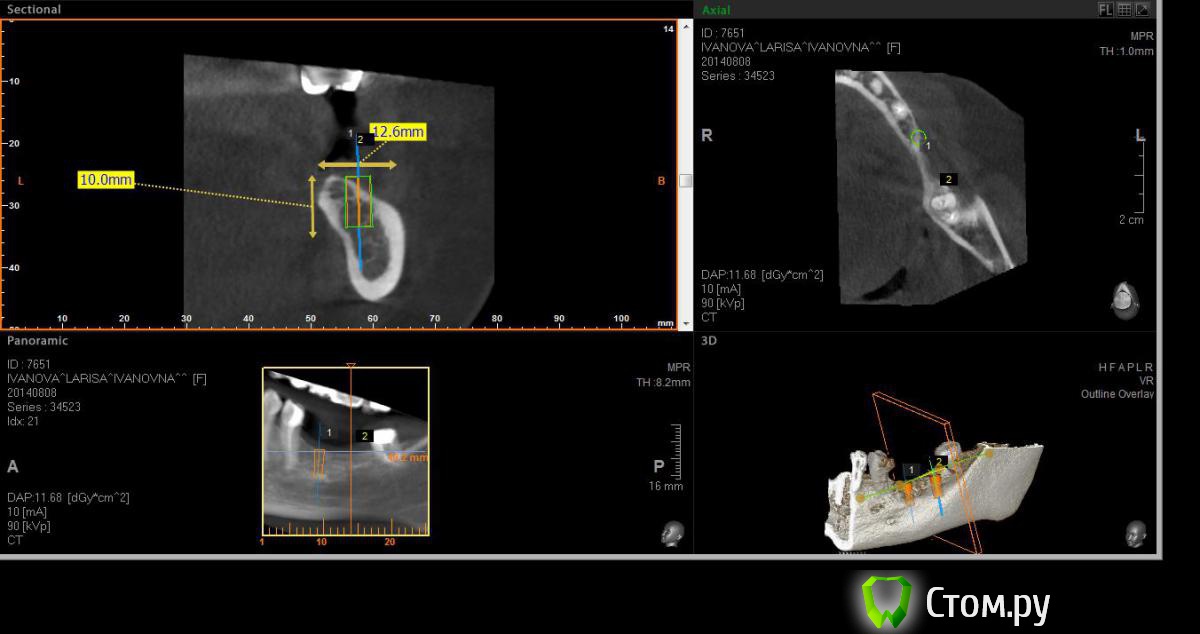

Neilrus Опубликовано 19 августа, 2014 Поделиться Опубликовано 19 августа, 2014 (изменено) Здравствуйте, форумчане-коллеги ) подскажите в очередной раз, пожалуйста.Возник вопрос, для опытных, безусловно, простой, помогите добрым советом.планируем имплантаты в область 36, 37. Длина никак больше 8 не входит, до нерва 10 с копейками и боюсь слишком тонкую кортикалку подязычно оставить.Расщепление из-за формы гребня не думаю, что получится, что-нибудь отломаю точно, хочу поставить как на фотографиях с нкр, голые витки вестибулярно перекрыть еволюшином толстым, припинить весибулярно и язычно если подлезу, либо подошью там.Как вы считаете, рабочая стратегия? Основной вопрос, могу я тут 100% ауто использовать? Объем же не большой, тут со сверления наберу, либо скребочком в зоне операции, заодно и принимающее ложе освежую это же сосидж? ничего не перепутал? И по поводу диаметров, 36 будет 3,75х8, а 37 4,2х8, не кротковаты? Просто у нас только МИС seven пока, либо 8, либо 10 длина. В 37 можно и 5 диаметр поставить, но опять же тонкая язычно остается. По той же причине отказался от длины 10 в 36зубе. Изменено 19 августа, 2014 пользователем Neilrus Ссылка на комментарий

Maxfac Опубликовано 20 августа, 2014 Поделиться Опубликовано 20 августа, 2014 А по-моему, влезает туда десятка. 1 Ссылка на комментарий

kriokov Опубликовано 20 августа, 2014 Поделиться Опубликовано 20 августа, 2014 Я бы не стал использовать 100% ауто. Может абсолютно все исчезнуть к дню раскрытия.50/50 с Bio-oss. И опять же я не стал бы ставить 8 мм. Мис, зная мисовские цифры для обычной пришеечной резорбции кости. Что останется от 8 мм. после формирователя? И не севен на н.ч.+100, думаю, что если нкр и направление имплантатов на небный бугор, 10 мм может пролезть Ссылка на комментарий

Neilrus Опубликовано 26 августа, 2014 Автор Поделиться Опубликовано 26 августа, 2014 (изменено) +2 )) Во-первых, фиксация у Севена лучше, конечной фрезой на 50 оборотах понемногу наберете ауто. Если есть АСМ или Джилли - еще получите в области ретромолярки. Во-вторых, кости (на самом деле) "немного" больше, чем показывает конусник (это тоже плюс). Поэтому можно и 8, и 10 со стопером или под контролем. Ставьте на 0,5-1 ниже язычной. Выше ставить и обсыпать не рекомендую - разве что только под жесткую мембрану, иначе все уйдет. Язычно я бы не смещался, ставил как запланировано, по шаблону. И в обл. 37 до нерва более 11, так что все будет ОК. Потом придется поработать с мягкими тканями. Удачи!Спасибо. Поставил в итоге два севена десятки, у м4 резьба у шейки никакая по мне так, а шейка тут важна. Наклонил все равно слегка язычно, никуда не провалился, парестезии нет, немного у медиального было ей больно при дотягивании на 25 нютонах, сделал полоборота назад, ауто, потом микс с мр3, эволюшн три пина язычно, два вестибулярно. Швы в пн снимаю, пока полет нормальный, отек уже почти сошел. И по поводу взятия ауто, насколько я правильно понял всех лекторов моих, забор во время бурения только промежуточными сверлами, пилотное и финишное сверление всегда с водой. Нет? Изменено 26 августа, 2014 пользователем Neilrus Ссылка на комментарий